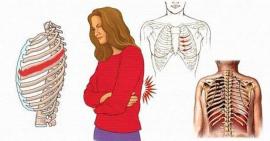

Cảnh báo nhiều bệnh lý nguy hiểm gây đau xương sườn

Đau xương sườn được thể hiện ở việc đau sườn bên trái hoặc bên phải. Những cơn đau có thể là đau nhói hoặc âm ỉ ở xương sườn....

1.388